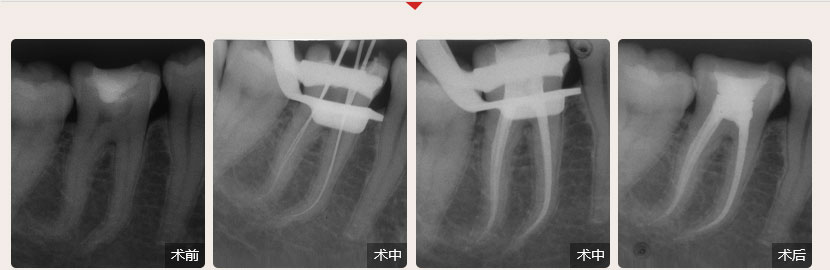

德倫口腔醫(yī)生全國根管治療技術(shù)競賽獲獎案例展示

性別:男        年齡:55歲

牙齒癥狀:急性牙髓炎(左下牙自發(fā)性、陣發(fā)性痛3天)        治療方法:顯微根管治療

疑難點評:操作方面使用根管顯微鏡和超聲波系統(tǒng)細(xì)致尋找和定位根管,根管的敞開度較為完美,維持了根管的原有走向,充填致密,流暢,充填長度準(zhǔn)確。

順德德倫口腔醫(yī)生全國根管治療技術(shù)競賽案例